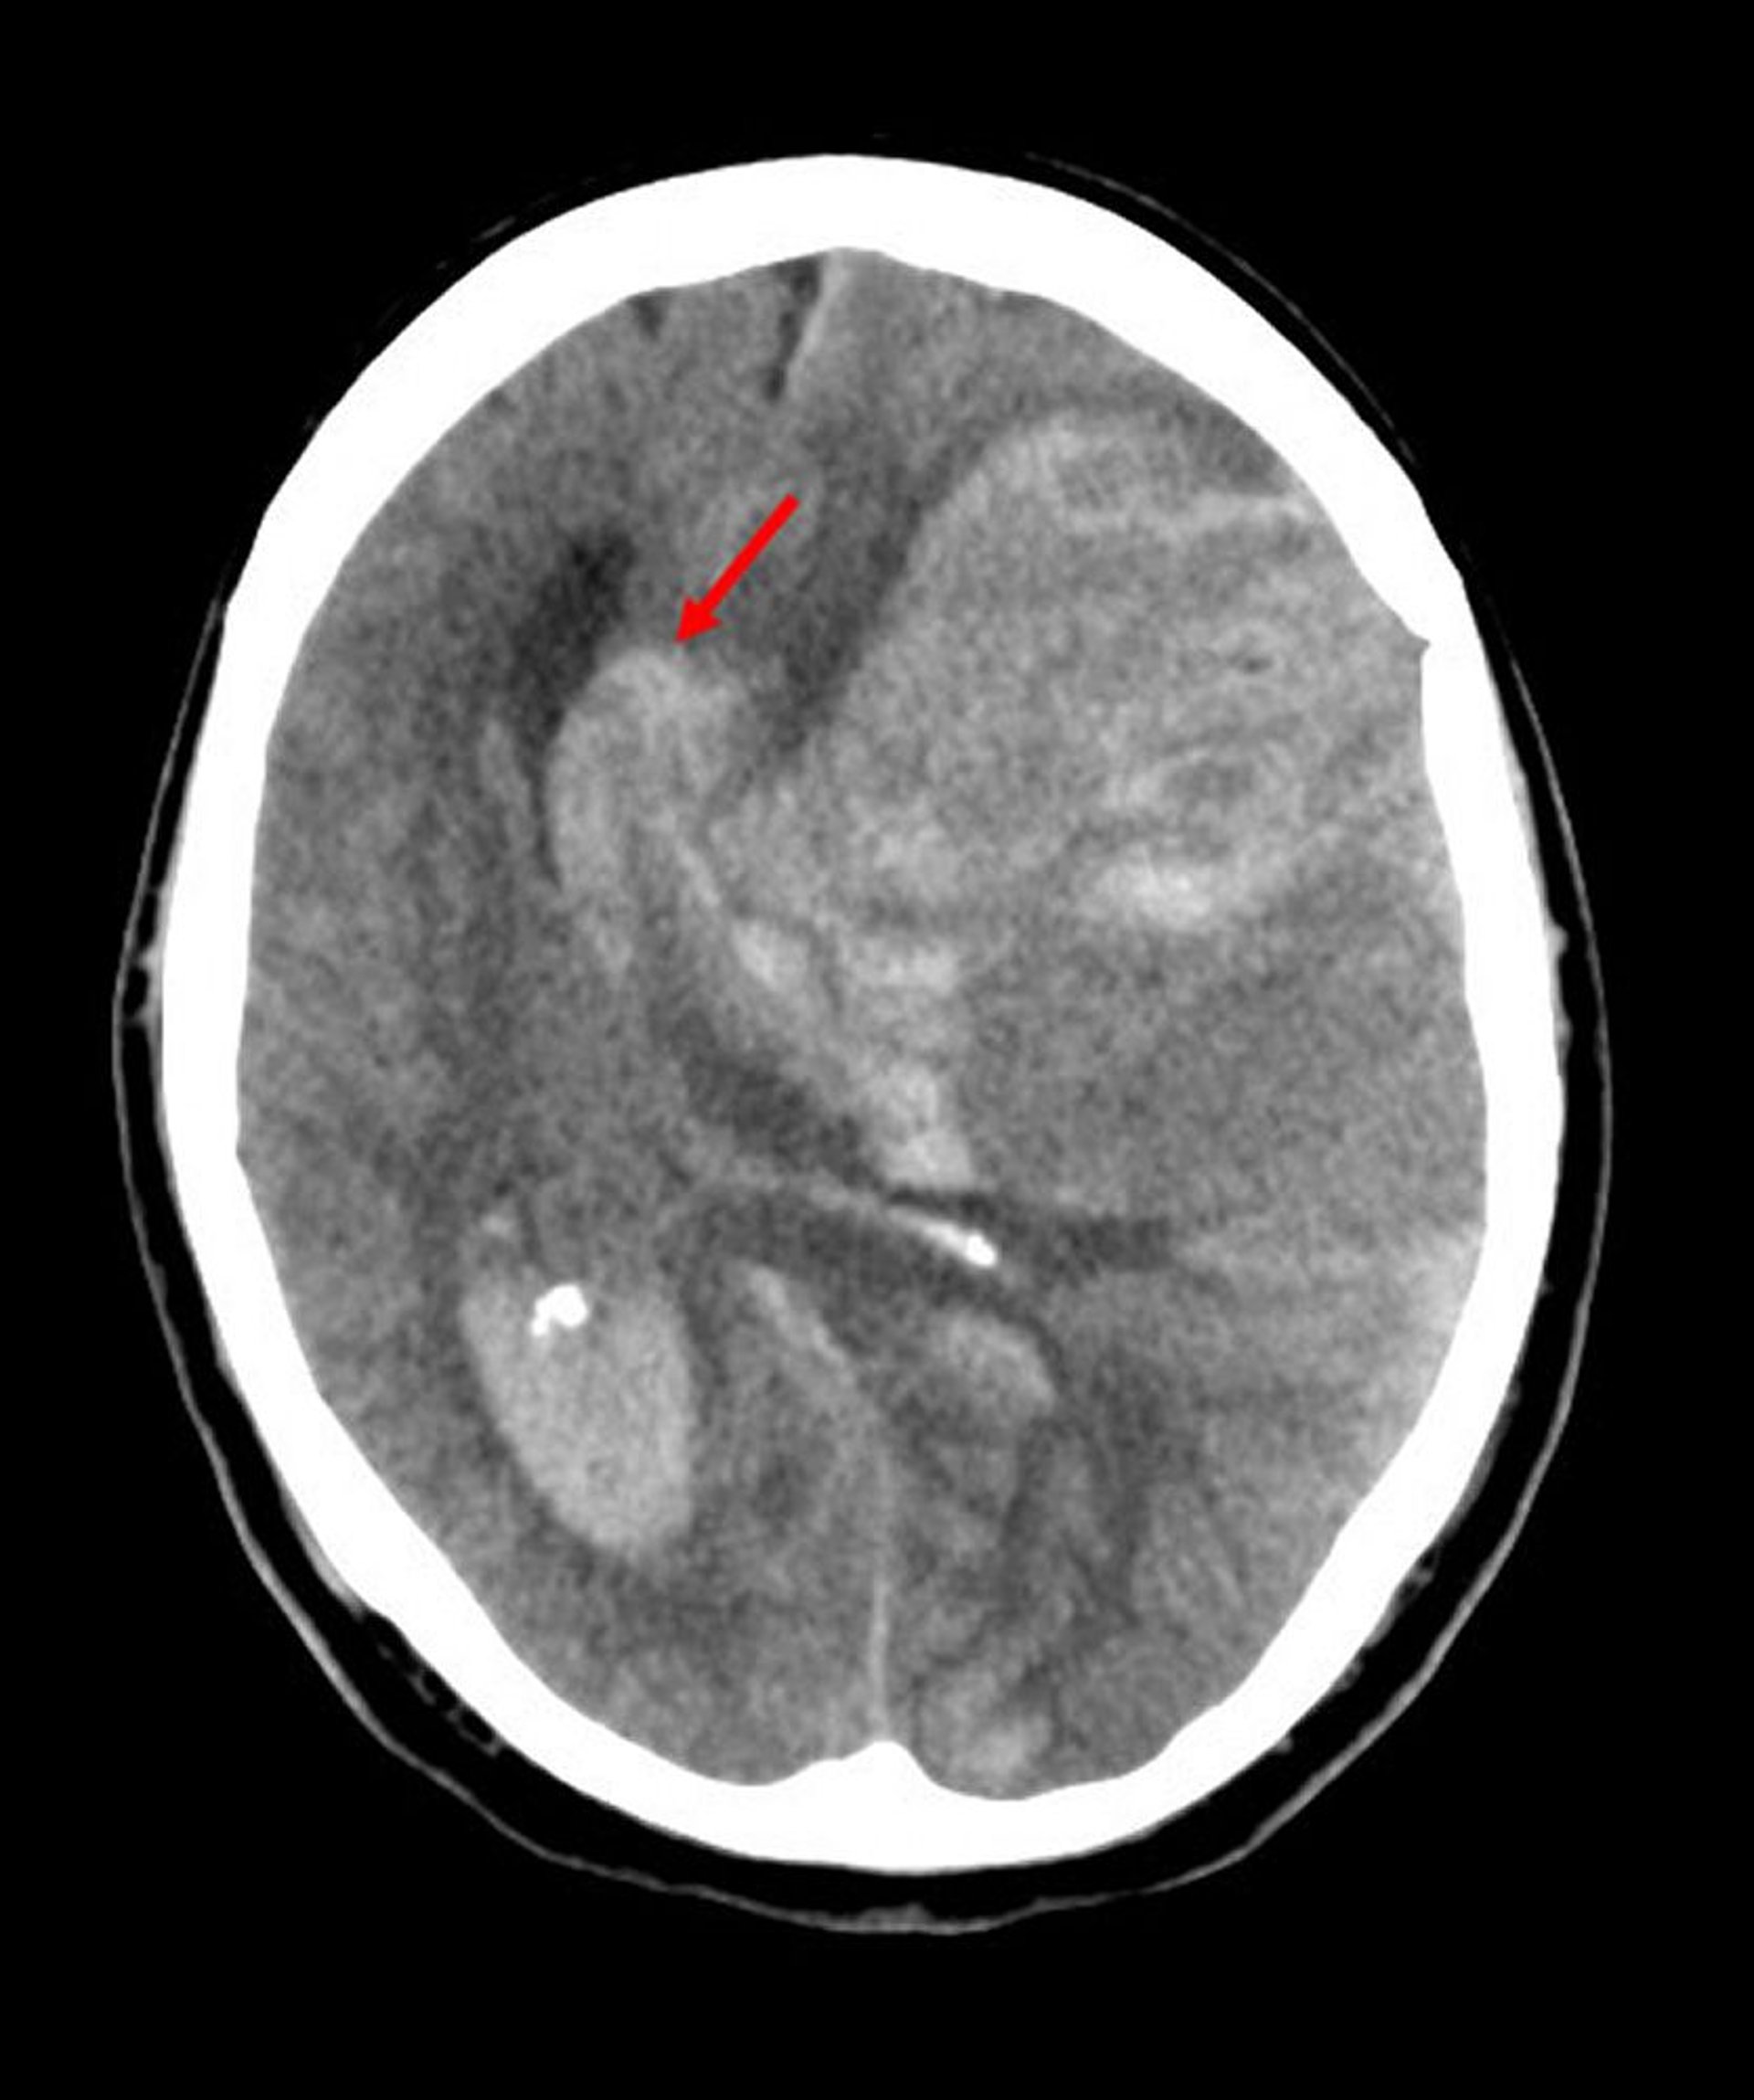

Engagement sous la faux du cerveau

L'engagement sous la faux du cerveau est le type le plus fréquent d'engagement cérébral. Dans cette image, le cerveau gauche s'est hernié sous le bord libre de la faux du cerveau (flèche) parce que l'hémorragie d'un infarctus de l'artère cérébrale moyenne a augmenté la pression intracérébrale.